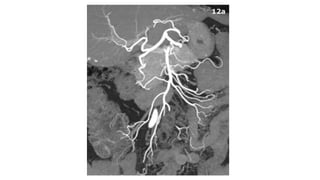

DIAGNOSTICO

• ARTERIOGRAFIA

• No solo confirma el Dx, sino que permite establecer su etiología

• Permite distinguir formas oclusivas de las no oclusivas

• Permite infusión de drogas vasodilatadoras como papaverina y

agentes troboliticos

DIAGNOSTICO • ARTERIOGRAFIA • Nosolo confirma el Dx, sino que permite establecer su etiología • Permite distinguir formas oclusivas de las no oclusivas • Permite infusión de drogas vasodilatadoras como papaverina y agentes troboliticos Moya Calvo M., Acosta Gacho G., et. Al.,Patologia del mesenterio, isquemia intestinal, Medicine, 2008;10(4), pp 231-241